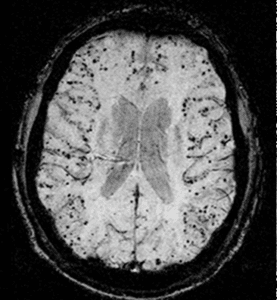

is it lymphoma?

The Great Mimicker

The ever lasting question, Is it lymphoma?

A Puzzling case!

Be prepared, this patient I don't have a diagnosis yet!

She is a 60-year-old with known past medical history of HLD and CKD. At her baseline before all symptoms started she had a normal cognitive function, no weakness no seizures, basically she was normal.

Symptoms started in October with nausea & vomiting for which she was admitted to a local hospital with negative workup. While there she developed DVT and was started on Eliquis. She was admitted walking and was discharged on a wheel chair. Family reported she started to have generalized weakness, mainly in her legs when these symptoms started. Couple weeks later with progressive weakness she presented to our ED.

Here, She was found to have areflexive weakness in both upper and lower extremity more in lower extremities with 2/5 muscle power. LP did show markedly elevated proteins (103 mg/dl) with normal cell count so a diagnosis of GBS was entertained and the patient was started on PLEX with minimal improvement.

At the end of PLEX course patient started to show gradual progressive cognitive decline and disorientation. MRI brain with contrast was normal. This was blamed on UTI that was treated with antibiotics and patient was discharged to inpatient rehab on 10/22.

While in rehab, patient continued to progress with increasing confusion, disorientation and abnormal movements (choreo-athetosis) involving both upper extremities. Neurology was called and asked to transfer patient back for further workup for encephalopathy. A repeat MRI brain with contrast was still unremarkable. LP was again negative for infections with normal cell count and elevated protein. IgG synthesis was normal but had only 2 oligoclonal bands unique to CSF.

Is it an encephalopathy related to Guillain Bare as in Bickerstaff encephalitis, or it is really not Guillain Bare and it may be all paraneoplastic neuropathy and encephalopathy or autoimmune disease with these elevated protein and 2 oligoclonal bands? She had significant GI symptoms prior to all of her symptoms, can this be part of DPPH VGKC?

Further tests were sent for Anti Gq1b, anti gangliosides, 14-3-3 and autoimmune encephalopathy panel (Mayo clinic ENC1). CT chest, abdomen and pelvis were negative. Patient was started on pulse steroids for empirical treatment of autoimmune encephalopathy without any improvement.

Exam:

- Awake, alert, not attentive, not oriented to time, place or situation.

- Speech markedly slurred, incomprehensible in most part. Still able to follow simple commands though.

- No cranial nerve involvement. Normal EOM with no pursuit movement defect.

- Marked weakness 3/5 in both upper extremities and 0/5 in lower extremities with diffuse hypotonia and areflexia. Mute planter response.

- Abnormal movements, choreoathetotic movements in both upper extremities.

- Negative hyperekeplexia

Workup so far:

- MRI brain with contrast on 10/08 - 10/14 and 11/01 unremarkable. No restricted diffusion, no cortical ribboning and no white matter signal abnormality, no significant brain atrophy.

- CT chest, abdomen, pelvis unremarkable

- CSF: 10/09 with 1 WBC - 2 RBC - 60 glucose - 103 protein. 11/02 with 1 WBC - 44 RBC - 58 glucose - 125 protein - 2 OCB (7 CSF and 9 serum) - normal IgG index and synthesis rate - negative meningitis PCR panel

- TSH, ammonia, B12, B1 and electrolytes were all normal

- SPEP with IFA: unremarkable

- B1 53 (mildly decreased -> repleted) - Copper 1.59 (mildly elevated) -

- HIV, HTLV, crypto Ag and PCR negative

More advanced tests:

- Ganglioside panel negative for GQ1b but positive for GD1b (GD1b is associated with Guillain Bare, GQ1b is associated with Bickerstaff encephalitis)

- Autoimmune encephalopathy panel in CSF and serum negative

- Paraneoplastic panel negative

- Anti MOG negative

- Anti MAG negative

- CSF tau elevated, 14-3-3 came back elevated but CSF RT-QuIC negative

- EEG x2 with one prolonged: negative apart from delta-theta slowing - no PSWC

My working differentials were:

• Guillan Bare that developed Bickerstaff encephalitis: no pyramidal signs, no cranial nerve involvement, negative GQ1b.

• Autoimmune encephalopathy: Still possible although ENC1 and ENS1 panels were negative. No response to steroids or PLEX. Normal MRI brain, no seizures.

• Paraneoplastic encephalopathy: Still possible although CT chest/abdomen/pelvis are negative. Paraneoplastic and autoimmune encephalopathy panel in serum and CSF (which includes paraneoplastic causes as well) negative

• CJD: that was the diagnosis I was waiting for. MRI and EEG findings are usually negative in the beginning of the disease so I ordered 14-3-3 which came back positive with elevated Tau, however RT-QuIC is negative !!

What do you think?

Any other differentials I should have looked at?

What should we make with the 14-3-3 result with negative Rt-QuIC, may be she needs olfactory mucosa RT-QuIC? but how it is going to change treatment?